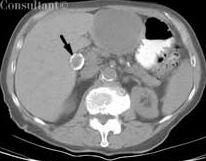

Porcelain Gallbladder

Virendra Parikh, MD

<div id="article-content-body"><p>During an evaluation to detect metastatic disease in a 75-year-old woman with recently diagnosed cecal cancer, a CT scan of the abdomen and pelvis...